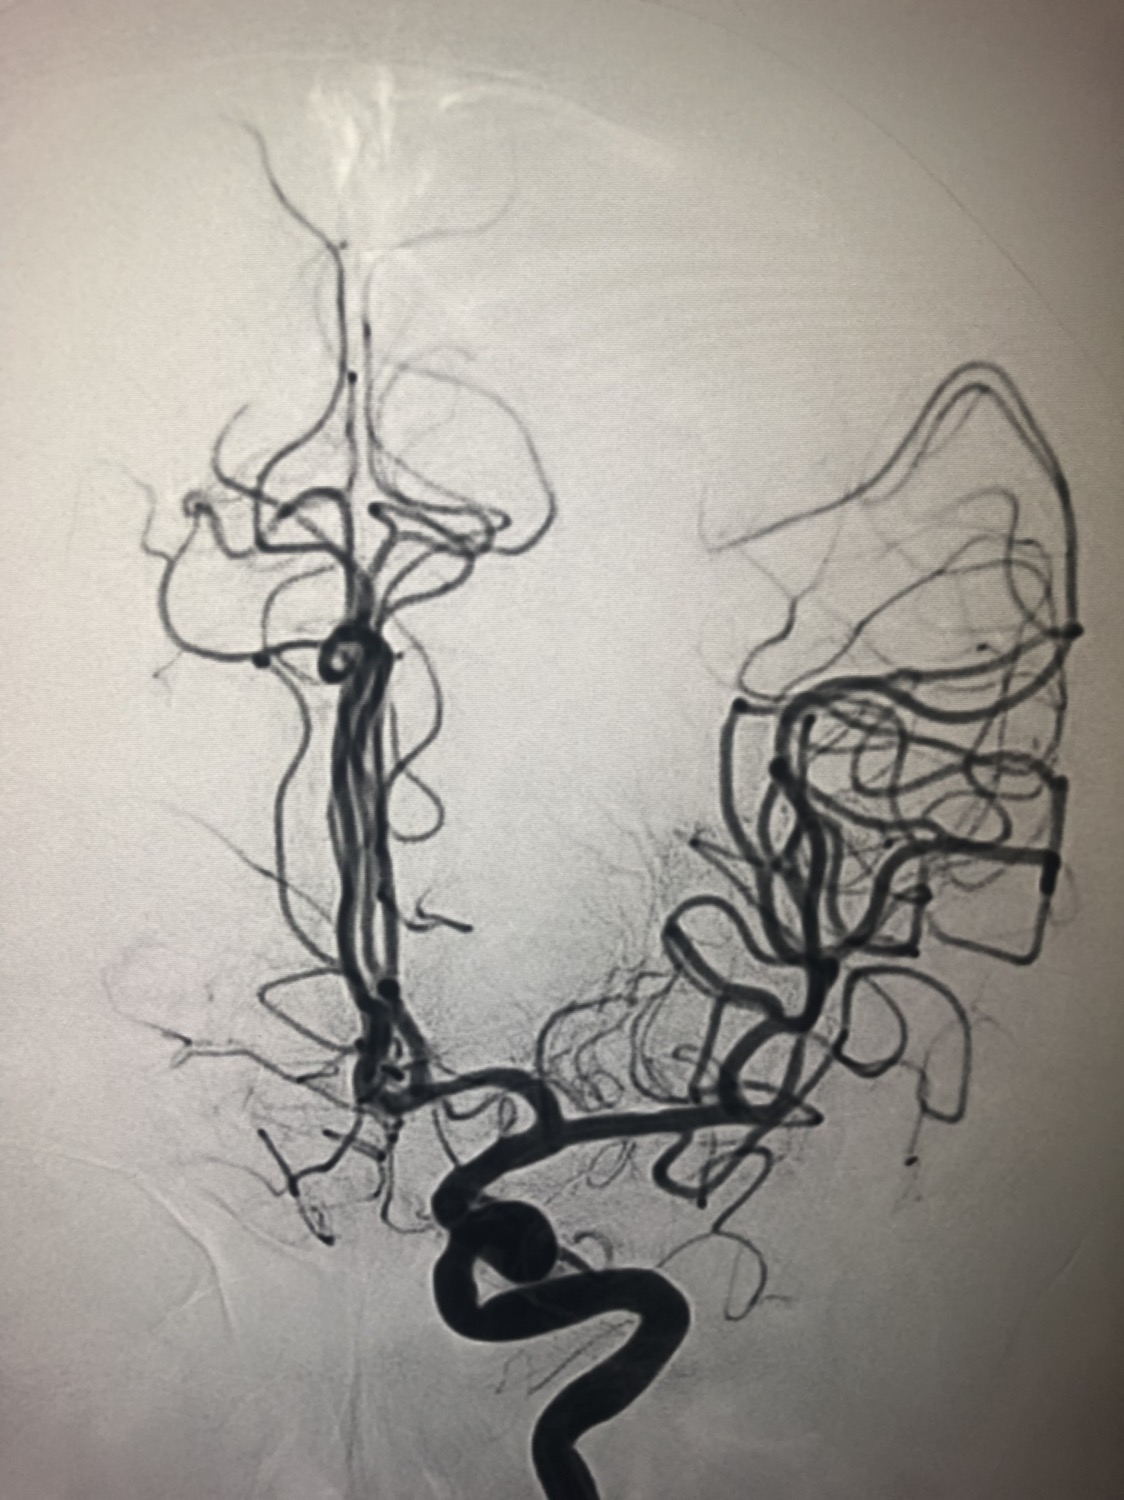

1周前房颤栓塞肱动脉,切开取栓后服用利伐沙班3天。突发偏瘫凝视3小时。上台看M3、A3血栓,国产普威森6f125cm抽吸导管高到位结合尼科3x20mm小支架,结合精细操作,m3和a3的血栓也可以轻松取出。不刺激血管。加造影射线16min两次取栓两个血管再通。

术后良好。